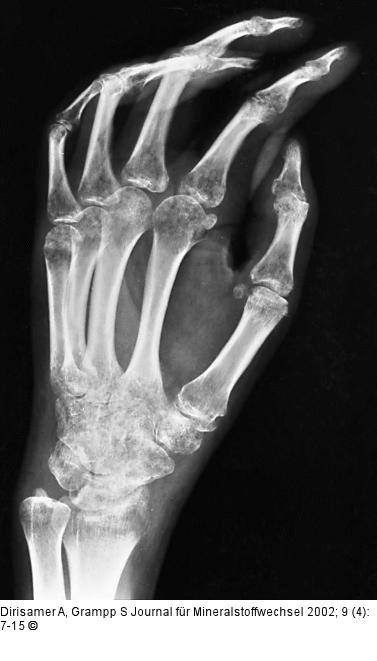

Abbildung 7: Osteoporose - Radiologie

Reflexdystrophie